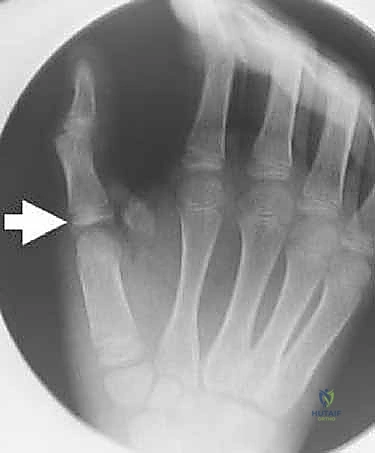

2. التصوير بالأشعة السينية (X-rays)

يُعد التصوير الشعاعي الخطوة الأولى لاستبعاد وجود كسور مصاحبة. في كثير من الأحيان، ينسلخ الرباط ويسحب معه قطعة صغيرة من العظم (Avulsion fracture). كما يتم أخذ صور أشعة تحت الإجهاد (Stress X-rays) لتوثيق عدم الاستقرار.